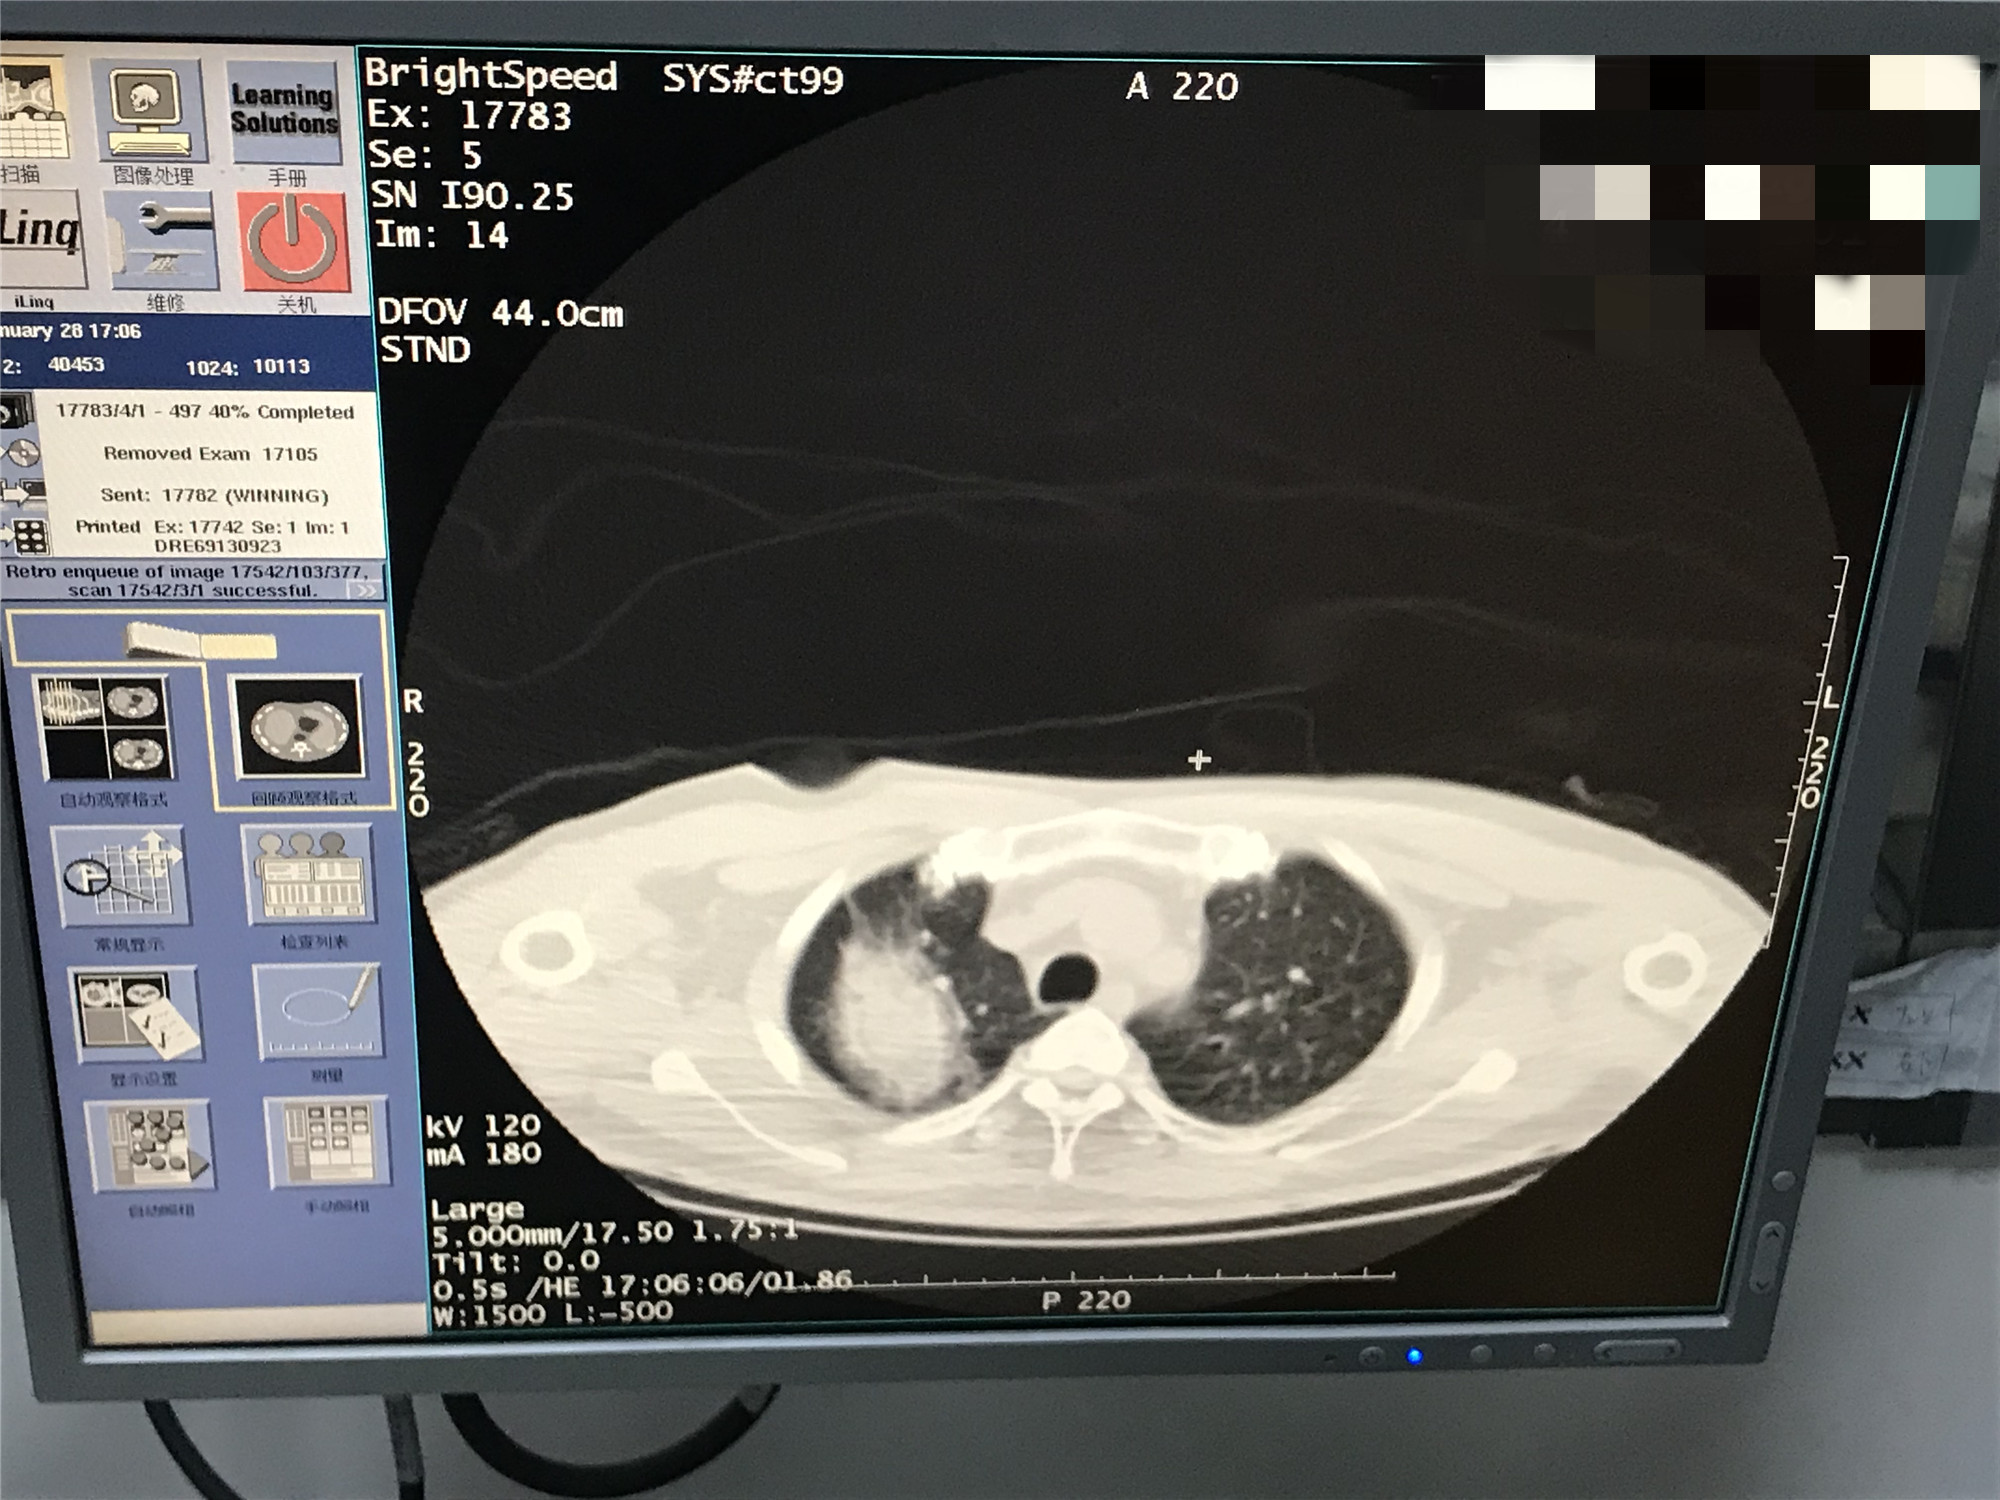

2021年1月份肺部氩氦刀手术